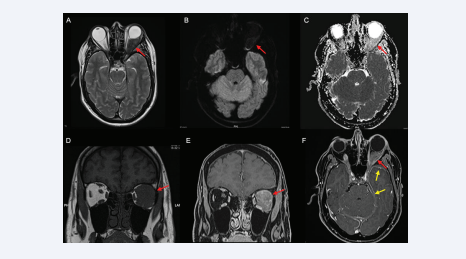

MRI depicting a left orbital retrobulbar mass hypointense on T2-weighted imaging due to its fibrous nature (A), without restriction on  diffusion-weighted imaging (B and C) and spontaneously hypointense on T1-weighted imaging (D) with strong homogeneous enhancement depicted  on the fat saturated post-contrast T1-weighted images (E and F) (red arrow). The lesion involved the left lateral and superior rectus muscles, with  anterolateral extension to the ipsilateral lacrimal gland and posterior extension to the cavernous sinus. A smaller soft tissue enhancing lesion was  also documented in the right orbital apex with extension to the right cavernous sinus, with the same signal characteristics and, intracranially, leftpredominant bilateral temporal and tentorial pachymeningeal thickening was better depicted (F; yellow arrow)

Figure 2: MRI depicting a left orbital retrobulbar mass hypointense on T2-weighted imaging due to its fibrous nature (A), without restriction on diffusion-weighted imaging (B and C) and spontaneously hypointense on T1-weighted imaging (D) with strong homogeneous enhancement depicted on the fat saturated post-contrast T1-weighted images (E and F) (red arrow). The lesion involved the left lateral and superior rectus muscles, with anterolateral extension to the ipsilateral lacrimal gland and posterior extension to the cavernous sinus. A smaller soft tissue enhancing lesion was also documented in the right orbital apex with extension to the right cavernous sinus, with the same signal characteristics and, intracranially, leftpredominant bilateral temporal and tentorial pachymeningeal thickening was better depicted (F; yellow arrow)

The lesion displaced the left optic nerve medially and the globe inferiorly. A right infiltrating orbital apex lesion with similar imaging characteristics was also documented. Intracranially, temporal and tentorial pachymeningeal thickening was also noted.

On MRI, the orbital masses in IgG4-ROD frequently demonstrate low signal on T1 and T2-weighted images due to the presence of fibrosis, with avid enhancement in T1 post-gadolinium sequences [11]. Infra-orbital nerve enlargement has been shown to correlate well with IgG4-ROD [12]. Although some patients with trigeminal nerve involvement report facial paresthesia, many are asymptomatic probably because involvement is limited to the epineurium [13]. Our case did not have imaging findings suggestive of infraorbital nerve involvement.

Patients with IgG4-RD-associated hypertrophic pachymeningitis are more frequently men, with a peak incidence in the sixth and seventh decades of life [14]. Meningeal involvement may be contiguous with disease in the orbit or pituitary gland and these patients may show elevations of cerebrospinal fluid IgG4 level, indicating intrathecal production of IgG4. On MRI, the dura may show smooth thickening with homogeneous diffuse linear enhancement (as in the case presented), or focal nodular thickening, mimicking a meningioma, and may result in compression of surrounding structures, especially cranial nerves [15].